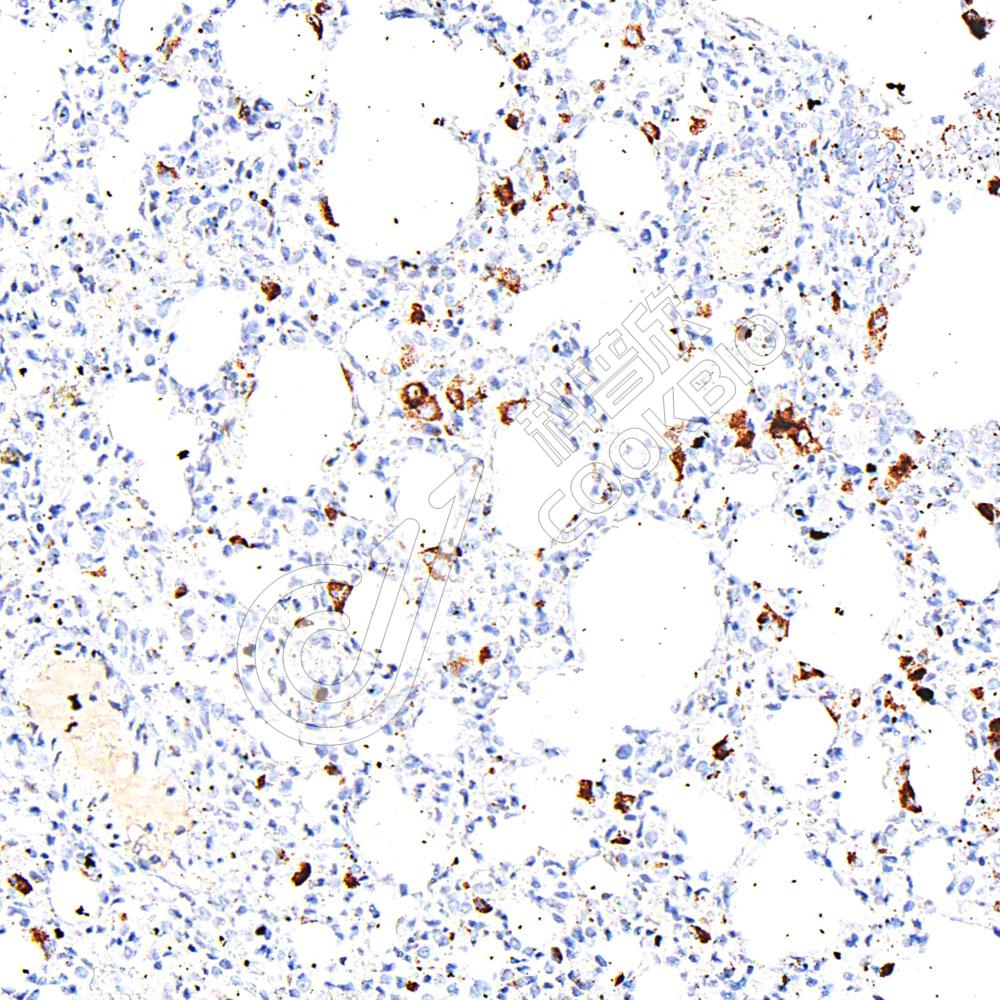

IHC检测p70 S6 Kinase蛋白(货号 K1333543).

样品: 人肝, 4%多聚甲醛 (货号KSG1101) 固定12-24小时.

抗原修复: 柠檬酸抗原修复液(干粉, pH 6.0) (KSG1201), 98℃, 20分钟.

—抗: 1: 1300稀释, 4℃ 孵育过夜.

二抗: S-vision免疫组化多聚二抗(山羊抗兔),即用型 (货号KB3906), 室温孵育20分钟.